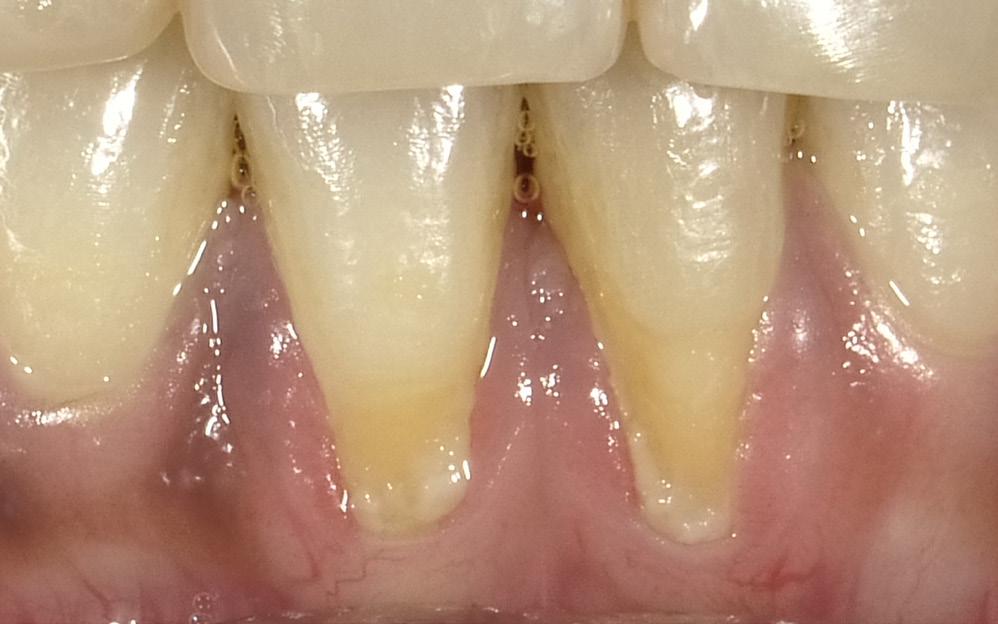

The data is clear; porcelain and composite resin are both biocompatible at the gingival margin and well tolerated.1-3 The caveat is that composite tends to cause tissue irritation if it intimate directly impinges on the gingiva.4-6 This ultimately causes unesthetic gingival recession.

Even skillful subgingival margin placement will typically, within 3-5 years, due to aging, gingival irritation, or lack of home maintenance on the patient’s part, lead to unesthetic recession and full visible exposure of the darker dentinal tissue.9, 10

Thus, the restorative conclusion is to locate composite margins supragingivally,3, 11 with the resin material reasonably away (0.250.50mm) from soft periodontal structures and thereby unlikely to cause tissue irritation.

A substantial increase in the apparent length of a tooth, specifically in the anterior labial region, detracts from the esthetic smile. When restoring a Class V decay or abfraction, or perhaps a small gingival recession, an enamel-colored resin is commonly placed at the labial DEJ. Increasing the maxillary central incisor’s vertical aspect (Fig. 1) by a mere 3mm adds 30% to the apparent vertical dimension, significantly altering the cervico-incisal to

mesio-distal (CI:MD) ratio, totally upsetting the esthetic parameters of the smile. (Fig. 2) In situations where there is moderate recession, the visual imbalance is even further impaired. The CI:MD ratio impact is even greater on maxillary laterals and mandibular incisors (average 9.0mm CI). Maxillary and mandibular cuspids (average 10-11mm CI) are often the teeth most affected by gingival recession, and are also highly visible both anteriorly and laterally.

Individuals who have gingival recession, abfraction and/ or decay tend to look older than they really are (long in the tooth). Covering the darker root dentin with an enamel-like resin simply makes their teeth more visible, seemingly longer, and correspondingly less esthetic.

Another important consideration is that the gingival margin of the restorative material (whether pink or enamel in color) must be kept supragingival and slightly away from the free gingival margin.3, 4, 6

This is the most commonly encountered recession in the oral cavity. The mandibular anteriors are small, close together, and not effectively cleaned by the tongue and

the lower lip. (Fig. 11) Due to gravity, food debris and plaque tend to accumulate labially and interproximally. (Fig. 12) In this case, the major culprit for the recession is the frenum that pulls the attached gingiva apically. The preliminary process is a diode laser frenectomy to eliminate the muscular forces.21-23

the buccal dimension and contour of the original soft tissue. Light cure. Leave a small (0.25-0.50mm) gap between the apical margin of the restorative and the free gingival margin. (Fig. 13) This procedure restores the expected gingival height, and contributes to making the patient’s smile look younger.